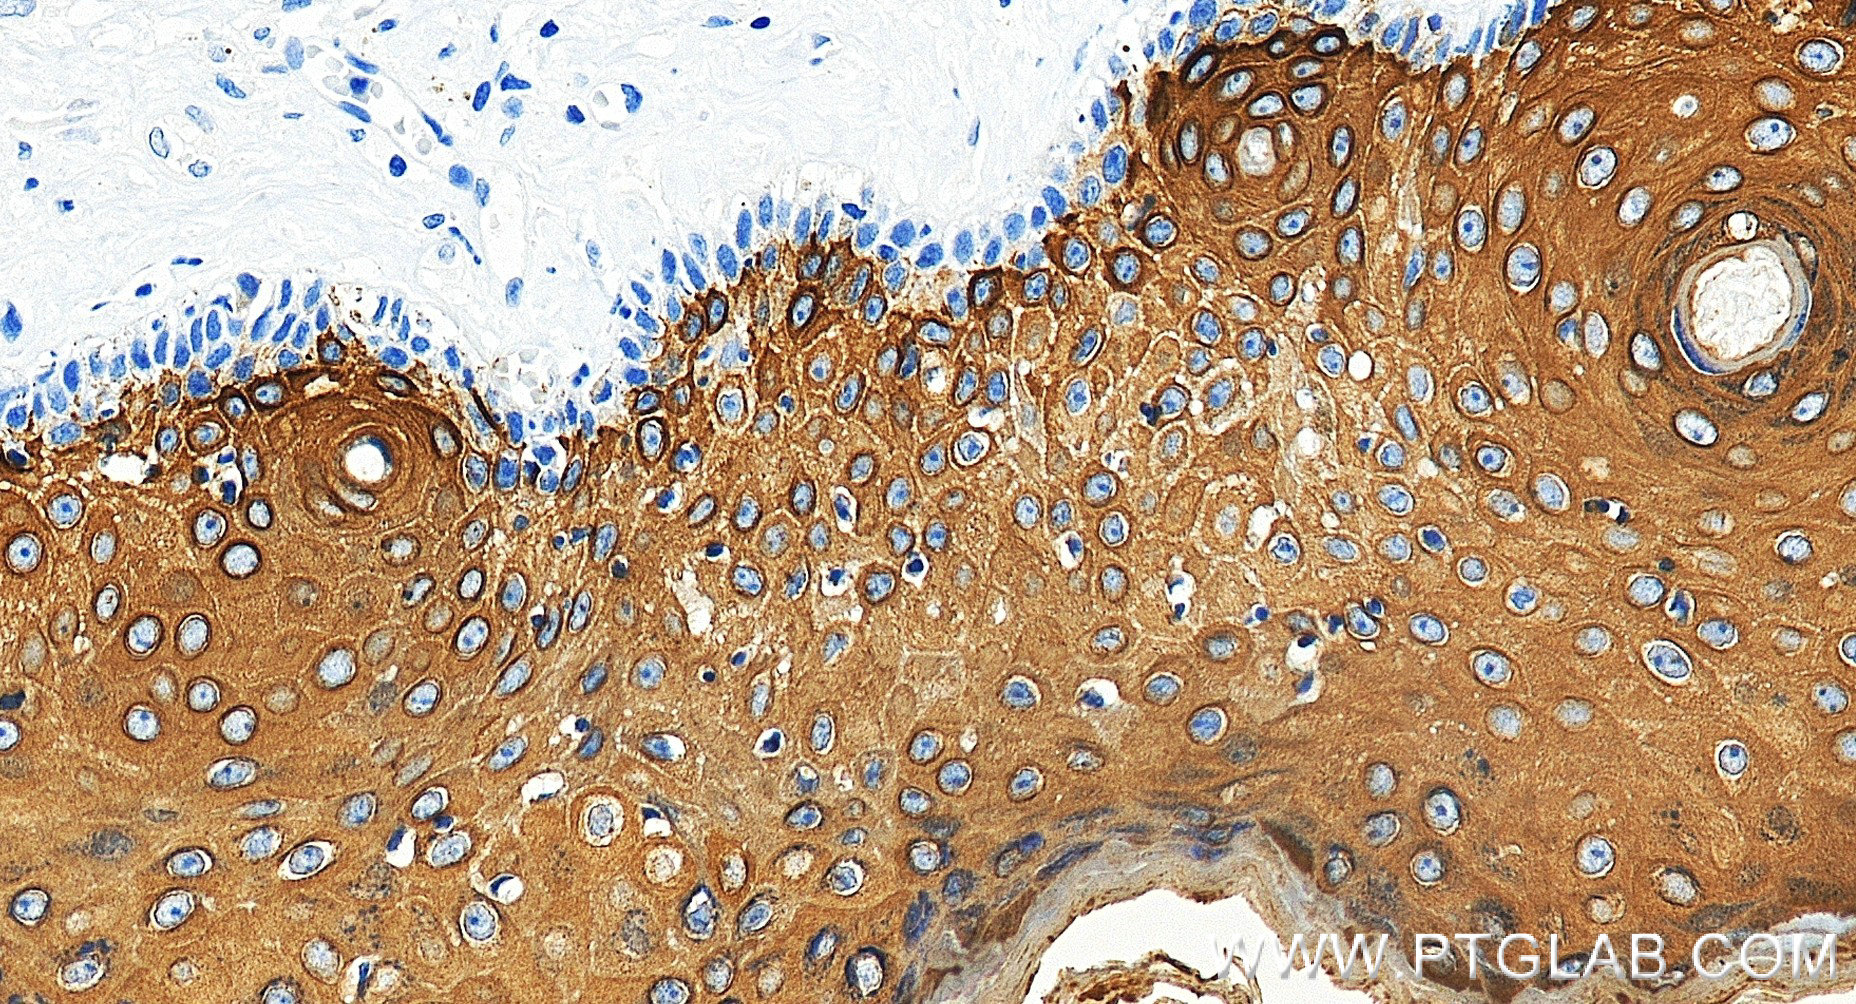

| Positive IHC detected in | human skin tissue, human skin cancer tissue Note: suggested antigen retrieval with TE buffer pH 9.0; (*) Alternatively, antigen retrieval may be performed with citrate buffer pH 6.0 |

| Immunohistochemistry (IHC) | IHC : 1:2000-1:8000 |

86324-1-RR targets Cytokeratin 10 in WB, IHC, IF-P, ELISA applications and shows reactivity with human, mouse, rat samples.

Cytokeratin 10 (CK-10, K10, KRT10) is a type I (acidic) cytokeratin and part of the intermediate filament protein superfamily. It is expressed in keratinized stratified epithelium, suprabasal cell layers (including the stratum corneum), and differentiated areas of highly differentiated squamous cell carcinomas. CK-10 plays a role in maintaining the structural integrity of epithelial cells and is involved in differentiation, tissue specialization, and epidermal barrier establishment. Mutations in the KRT10 gene are associated with epidermolytic hyperkeratosis, and its expression is linked to the terminal differentiation of epidermal cells . CK-10 is also used as a marker for tissue differentiation and characterization of malignant tumors in surgical pathology.